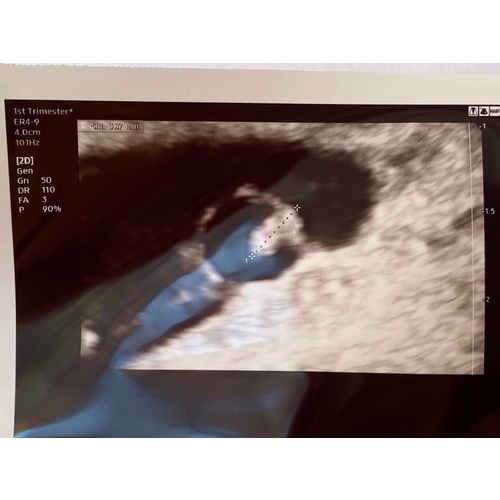

Wij hebben precies hetzelfde, al noemde onze verloskundige het niet zo. Gisteren hebben we de eerste echo gehad en waar ik dacht 7+4 te zijn heeft het vruchtje de grote van 6 weken. Er klopt ook nog geen hart. De vruchtzak is wel gegroeid en dus niet in verhouding met het vruchtje. Zaterdag moet ik terug komen om te kijken of er dan een hart klopt en we te vroeg waren of dat het is gestopt met groeien. De verloskundige vond het er niet goed uitzien en we moesten ons voorbereiden op een miskraam.

Ik heb dit dus ook, dat had je in mn andere topic gelezen. Ik had 8+4 moeten zijn, de echo zegt 5-6 weken zonder kloppend hartje. Wij moeten volgende week dinsdag afwachten 😔 vruchtje was 4,3 mm

Ik heb ditzelfde meegemaakt. Ik dacht dat ik 8 weken was, maar werd terug gezet naar 6+4. Ik kreeg 2 weken later bloedverlies. Echo gehad en geen hartje te zien en de stand was nog steeds 6+4. Bij mij was de vruchtzak ook groot genoeg voor kindje van 9 weken alleen was het vruchtje gestopt met ontwikkelen.

Vond het geel bijzonder ik moest officale 13 weken zijn, toen was ik 5,5 toen was het helemaal nog niet eens levend en toen ineens (nu dus) ben ik 7+2 dagen! Volgende week dinsdag 8 weken echo dus ben heel benieuwd

Wij hebben vandaag om 13:30 een tweede echo om te zien of het vruchtje qua groei gepauzeerd was of helaas gestopt. Ik weet niet of ik me nog zwanger voel. Alle "kwaaltjes" die ik ervaar (misselijkheid, vermoeidheid) kunnen net zo goed van een zwangerschap komen als van de warmte en spanning. Helaas wel sinds gistermiddag wat bruine afscheiding bij afvegen dus dat stemt niet echt hoopvol..

Ik heb zo om 9:15 echo om te kijken of alles nog goed is.. 2 weken terug gezet van 8 naar 6 weken inmiddels 7 weken en al 1,5 week bloedverlies. We gaan eigenlijk uit dat het niet goed is, kan het altijd nog mee vallen...